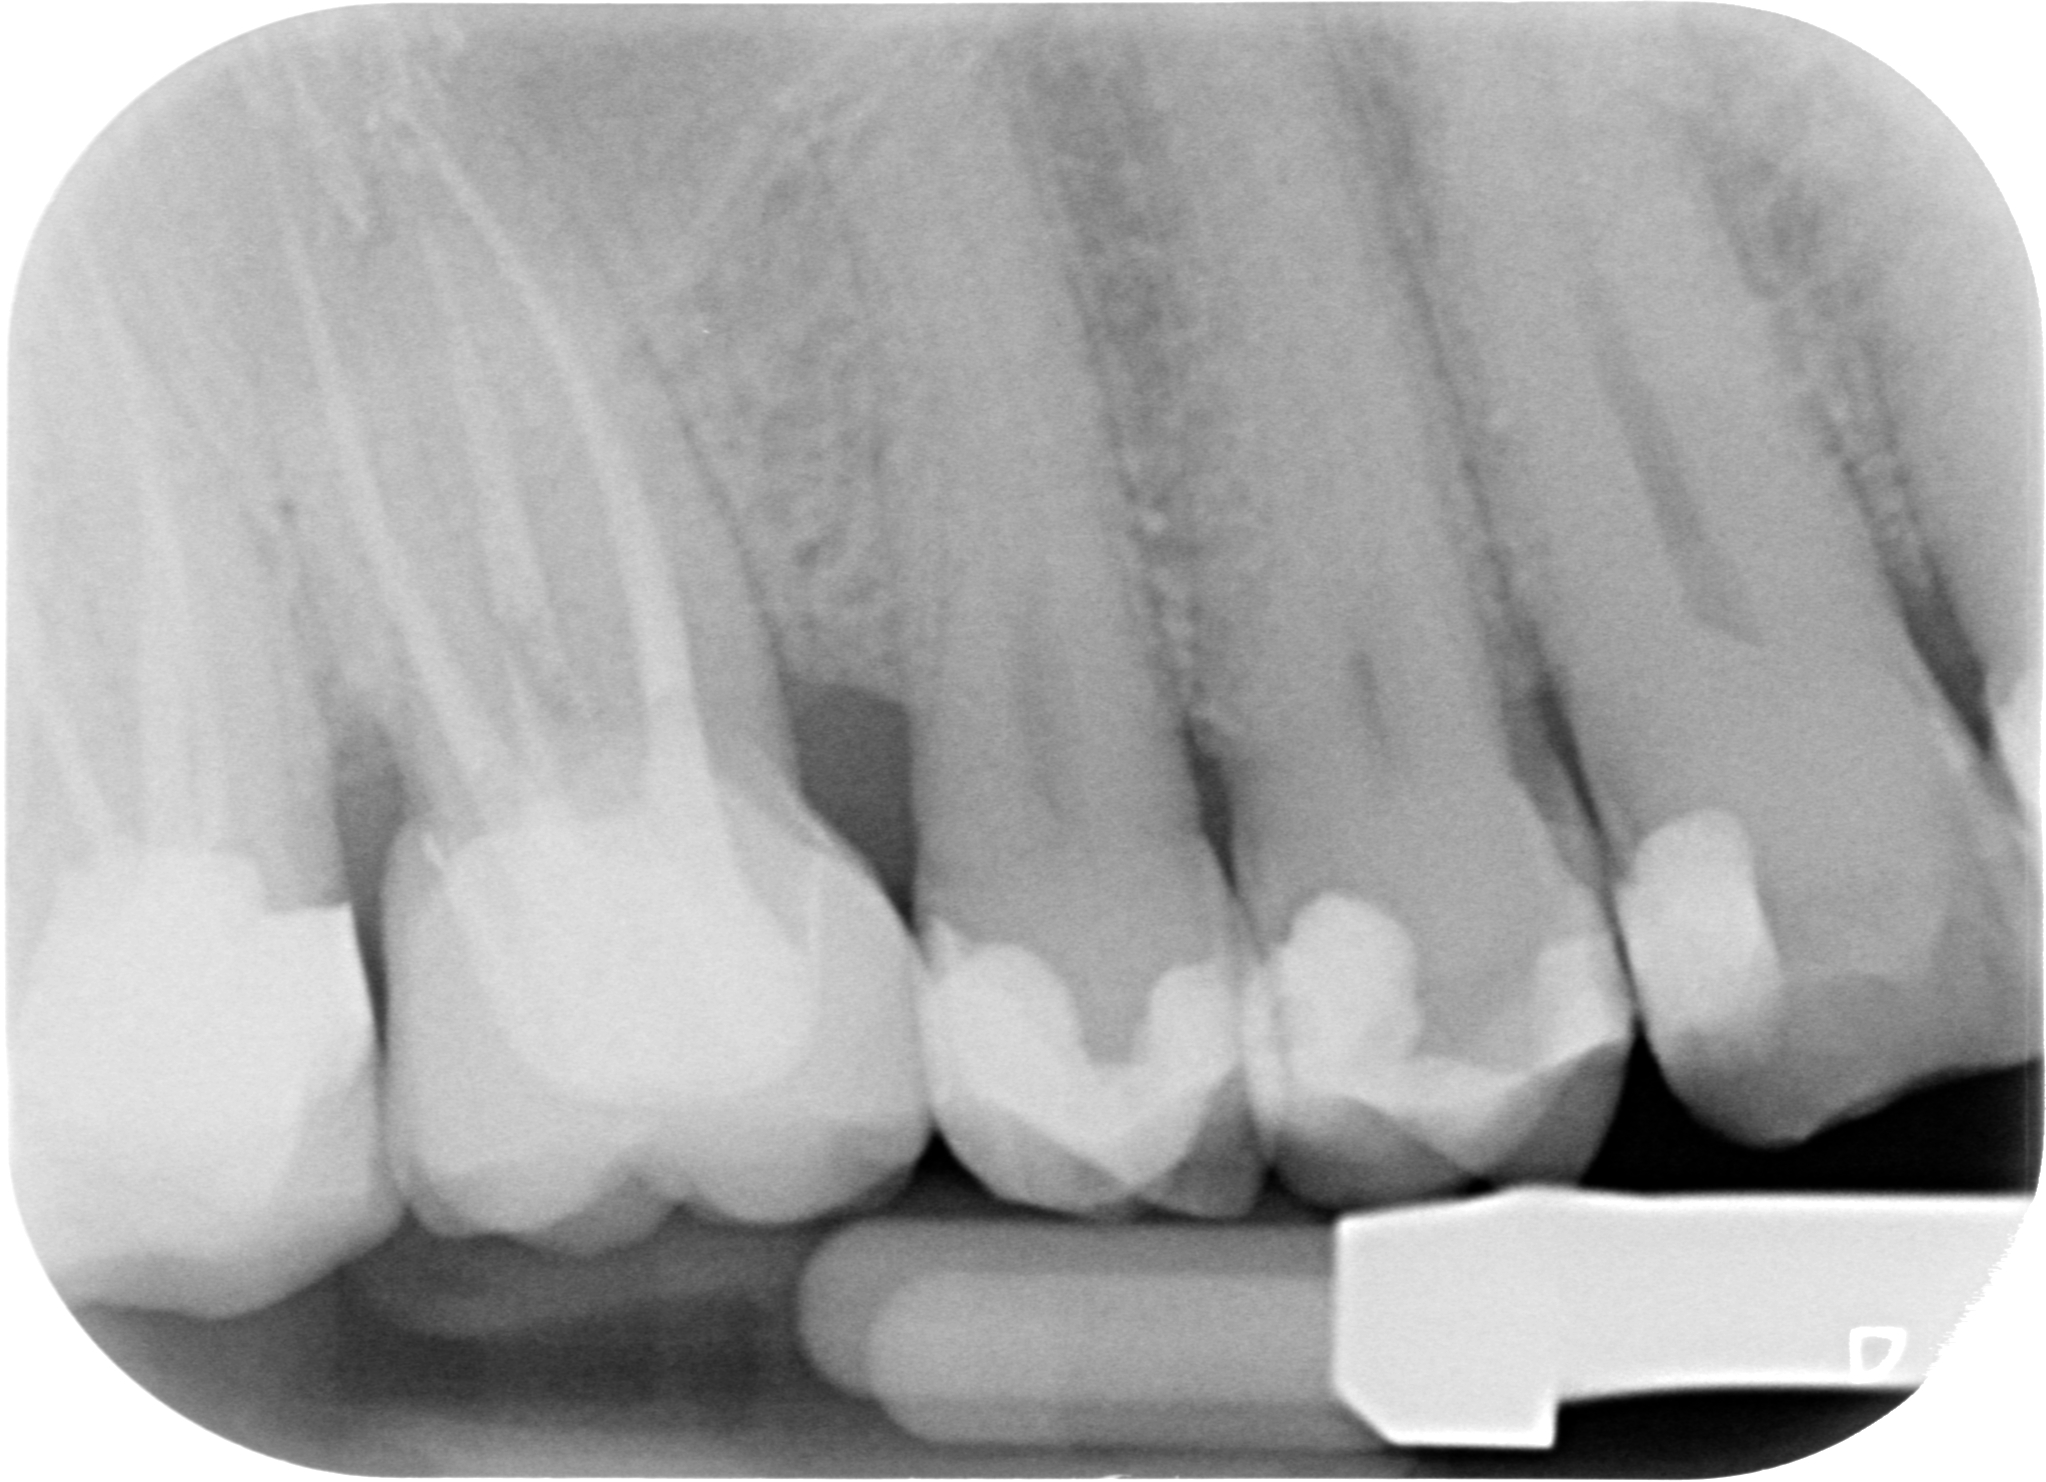

Il riposizionamento apicale dei tessuti parodontali ci consentirà quindi di:

ESEGURE UN CORRETTO RESTAURO PROTESICO

PS: l’allungamento di corona clinica non vuol dire aprire la papilla fresare un po’ di osso interprossimale e chiudere! Quello tecnicamente si chiama creare un difetto parodontale iatrogeno.